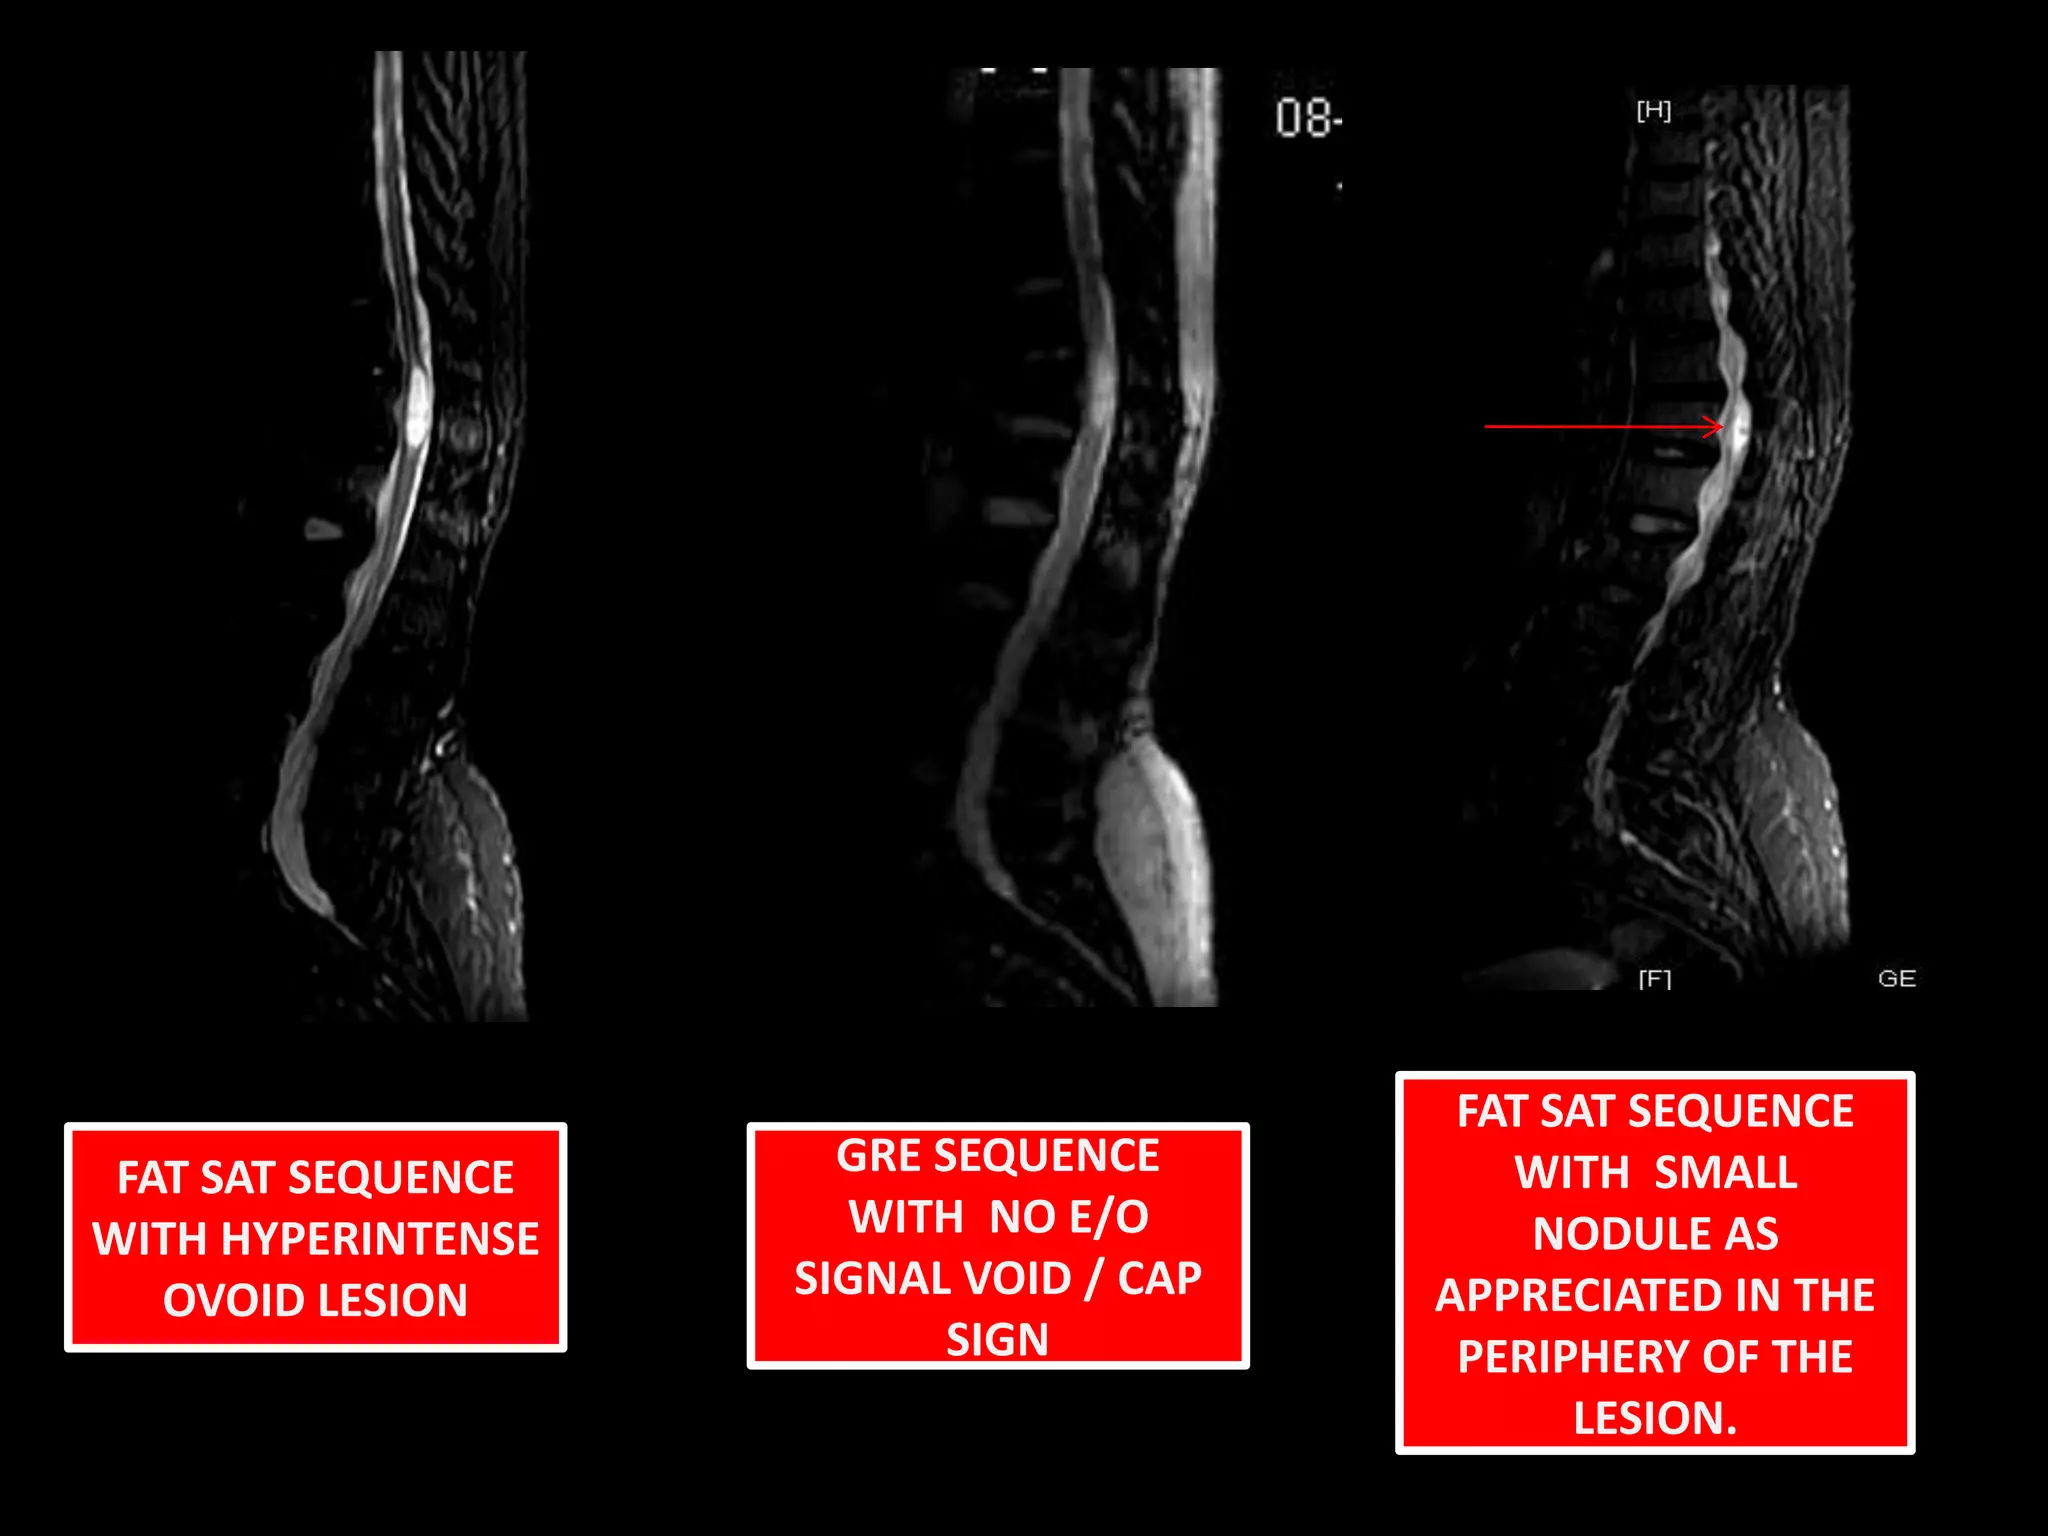

FAT SAT SEQUENCE WITH  SMALL NODULE AS APPRECIATED IN THE PERIPHERY OF THE LESION.FAT SAT SEQUENCE WITH HYPERINTENSE OVOID LESIONGRE SEQUENCE WITH  NO E/O SIGNAL VOID / CAP SIGN

FAT SAT SEQUENCEWITH SMALL NODULE AS APPRECIATED IN THE PERIPHERY OF THE LESION.FAT SAT SEQUENCE WITH HYPERINTENSE OVOID LESIONGRE SEQUENCE WITH NO E/O SIGNAL VOID / CAP SIGN